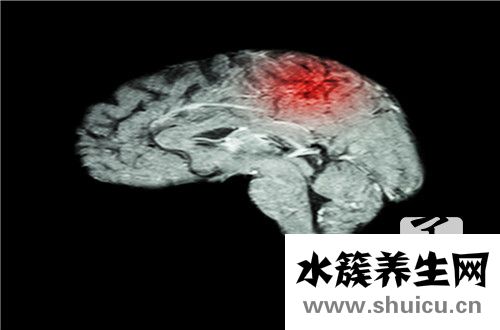

腦外科手術(shù)是一種危險(xiǎn)的重大外科手術(shù)治療。 手術(shù)前必須做一些準(zhǔn)備工作以清除腦積水。 通常,使用一些藥物或引流方法清除腦積水,兩周后即可清除。 更嚴(yán)重的患者大概需要二十天。 手術(shù)后,要注意患者的...